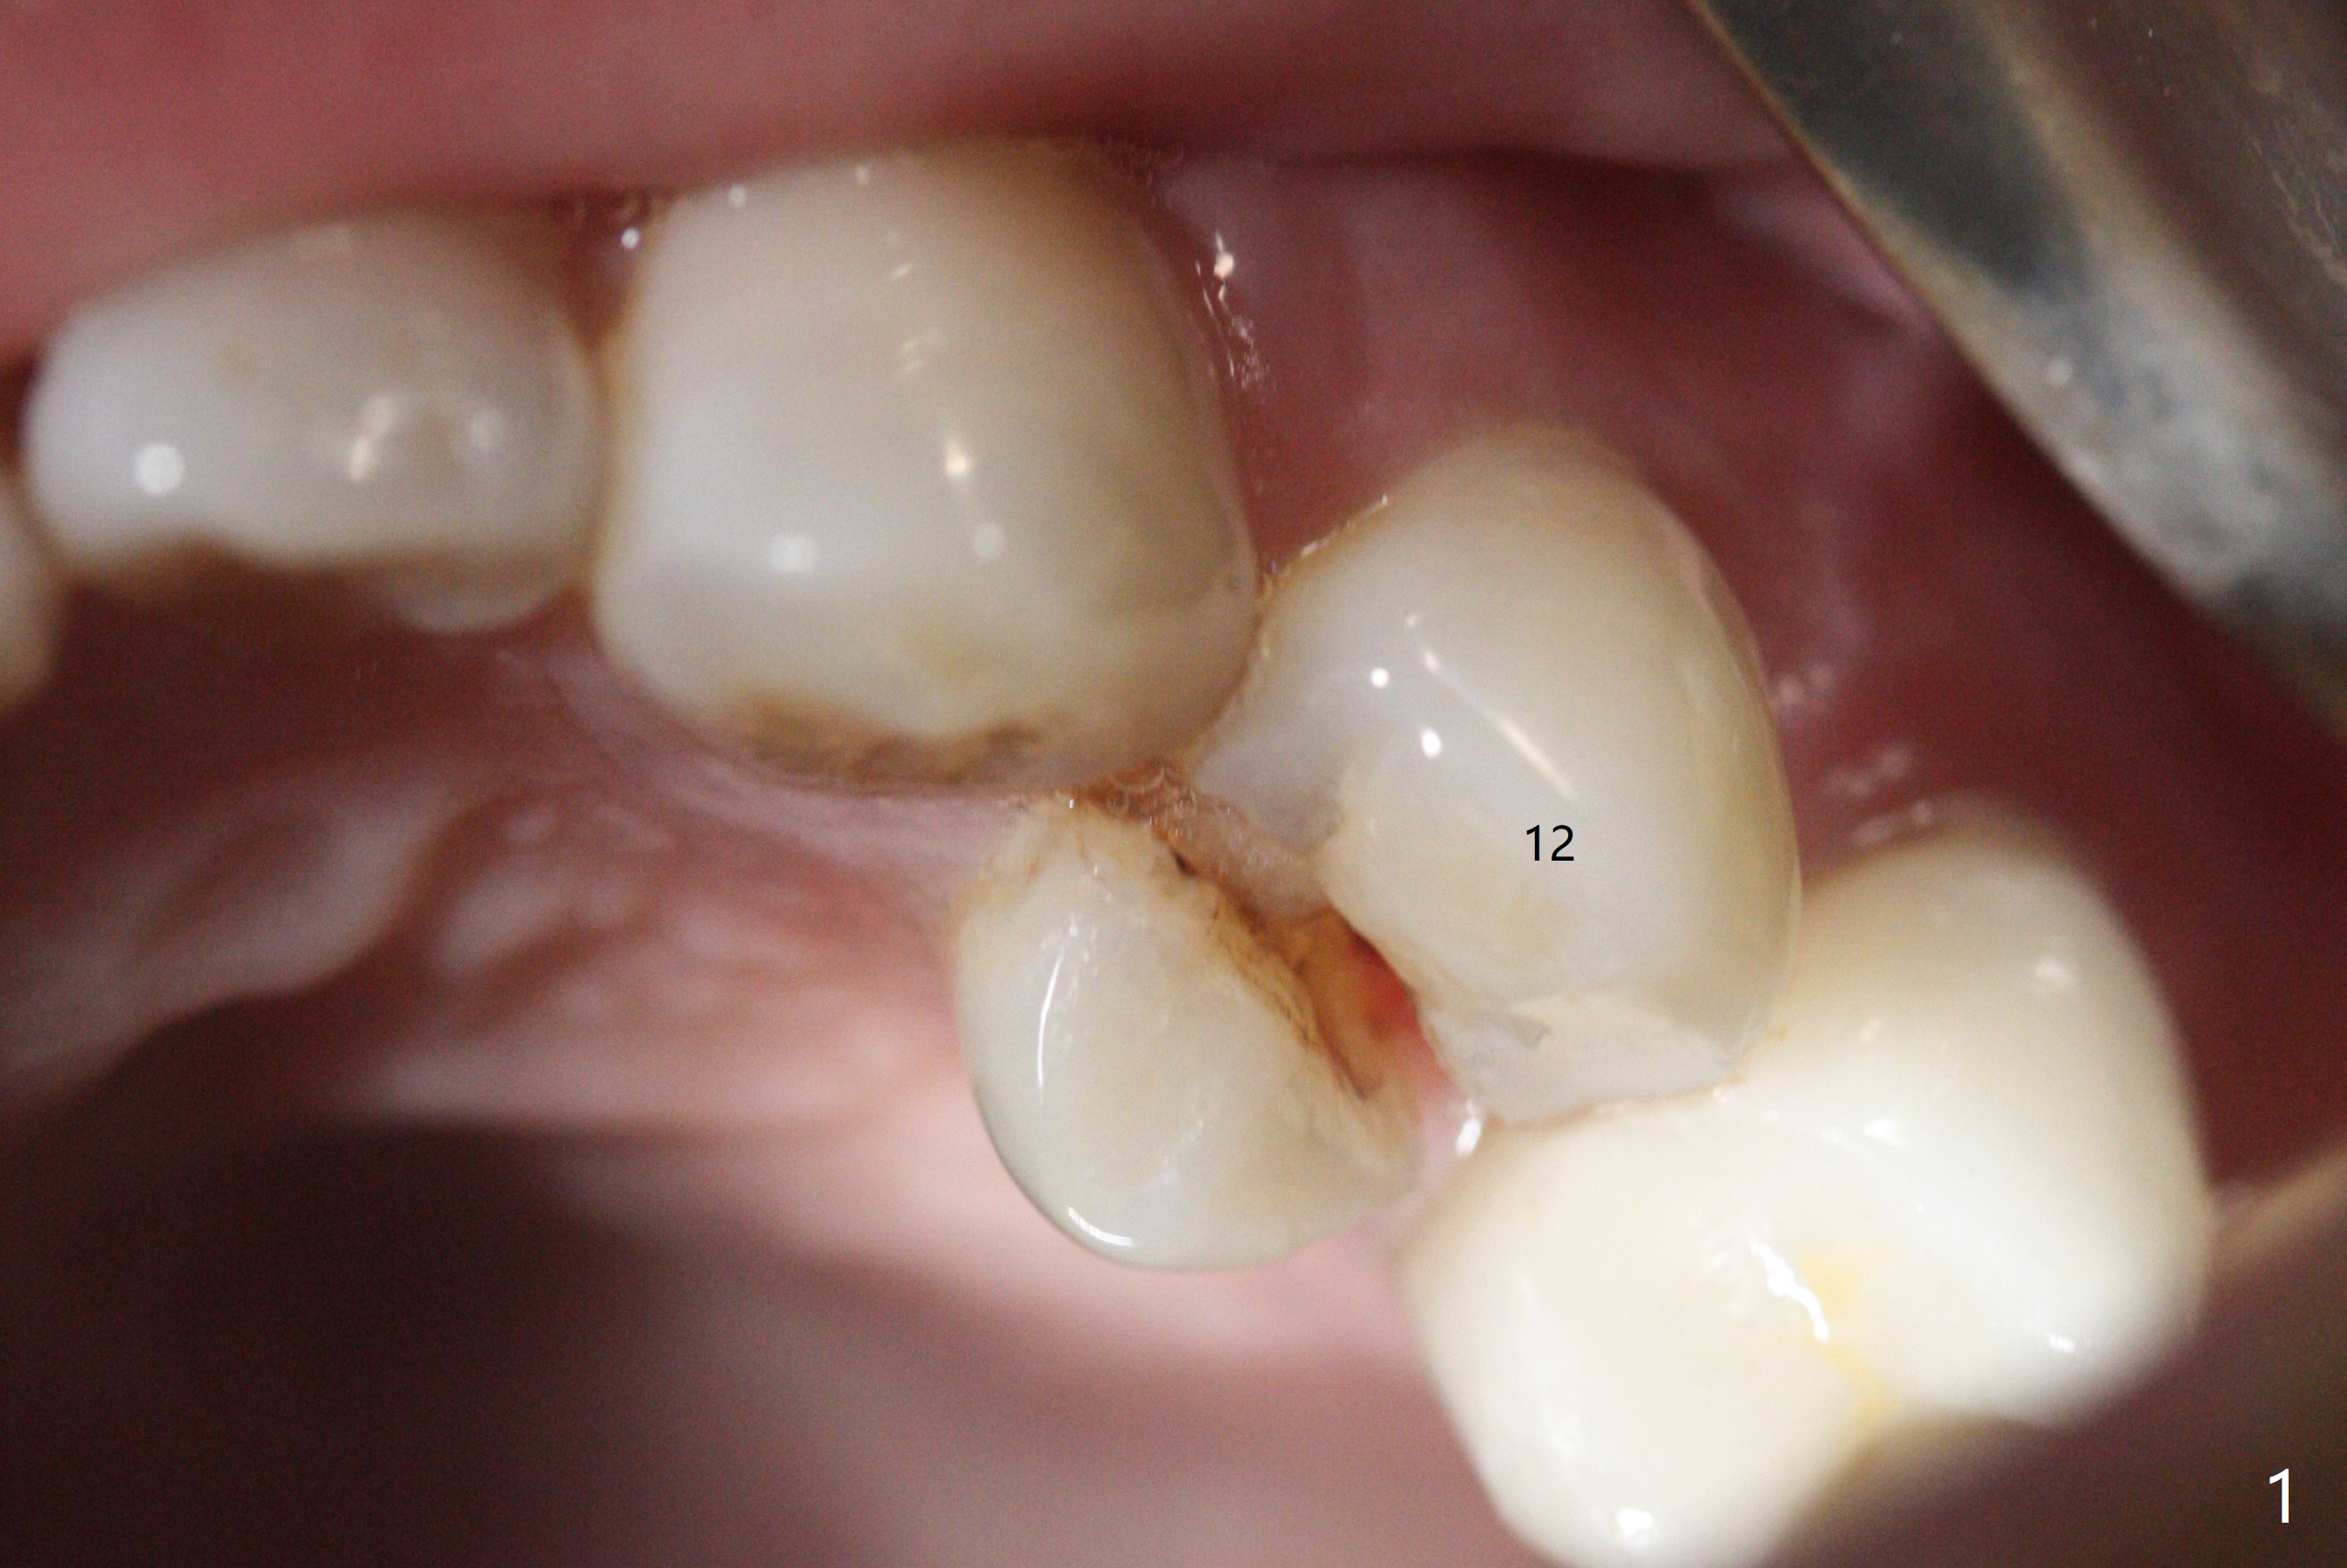

一个月前12号牙仅有隐裂(与术前即刻(图一)对比),当时CT显示轻度颊侧根尖缺损(图二:>)。拔牙后颊侧根尖没有骨板,所以钻洞偏腭侧(图三);完成最后钻头(3毫米)后,后者保持原位,先在颊侧根尖植骨,然后取出钻头,植入植体(图四),放置基台后,在后两者周围再置入骨粉,最后制作临时牙冠固定骨粉。由于骨质密度低(图二;术中钻洞容易),选择20毫米植体,扭力50Ncm。